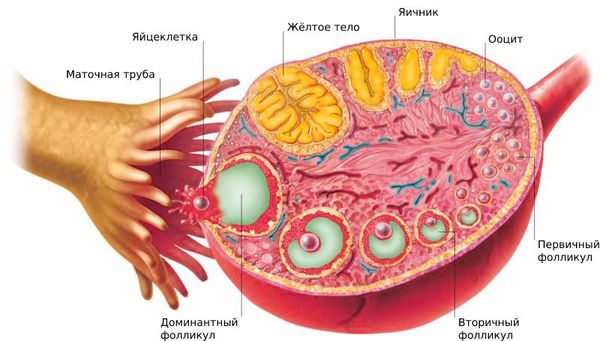

Созревание фолликула в яичнике: этапы и процессы